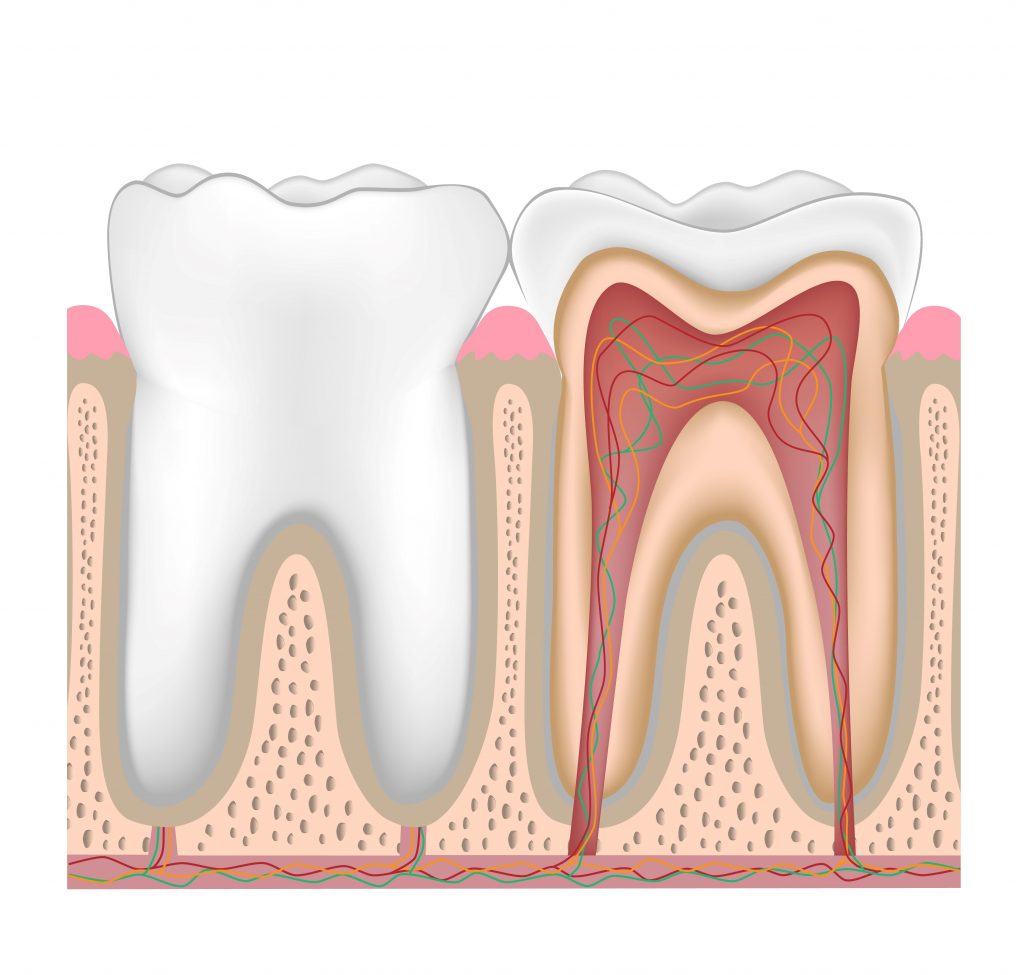

Before taking a close look at dental implants’ suitability, let us briefly remind you how dental implants work. Dental implants consist of two components: the implant and the crown. The titanium implant integrates the jawbone through the osseointegration process and the crown serves as the visible part of the tooth. First, the implant is placed into the jawbone and the patient waits for 6 months for the implants to integrate into the jawbone. After the integration, the crown is placed on top of the implant.

Dental crowns are highly durable and natural-looking dental restorations. Implants are a very effective solution for replacing missing teeth and have many advantages over other possible solutions, such as dentures. When performed correctly, they are a long-lasting, durable, and aesthetically pleasing solution.